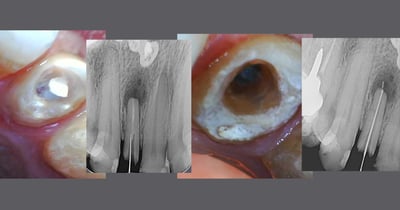

Tratamento endodôntico convencional

Tratamento de canal em dentes com quadros inflamatórios e/ou infecciosos em uma ou mais sessões.